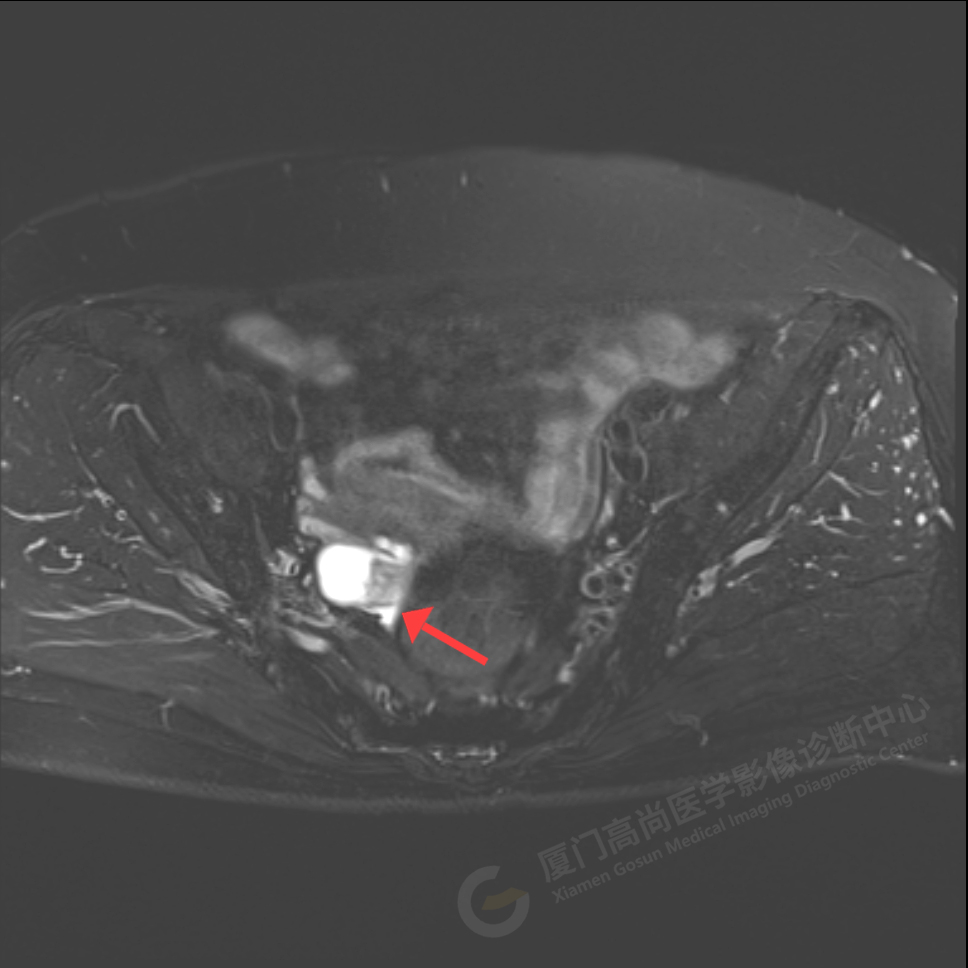

磁共振影像圖

我中心為陳阿姨安排了影像解讀及專家會(huì)診,經(jīng)過專家綜合分析,給出了初步診斷意見:右側(cè)附件區(qū)囊實(shí)性占位伴腫大淋巴結(jié),考慮卵巢來源惡性腫瘤,卵巢Ca可能性大。醫(yī)生建議盡快做進(jìn)一步的檢查及就診。

陳阿姨家人經(jīng)過多方打聽和聯(lián)系,陳阿姨于5月18日至廣東中山大學(xué)附屬腫瘤醫(yī)院會(huì)診及手術(shù),術(shù)后病理顯示:卵巢高級(jí)別漿液性癌2期,證實(shí)了高尚專家的判斷。